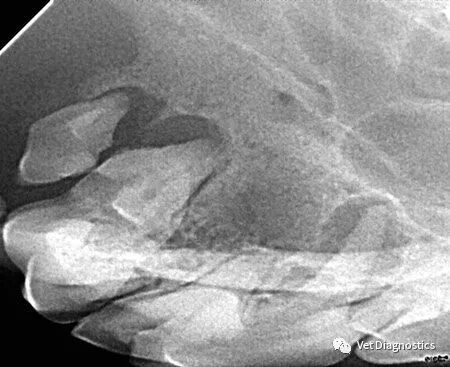

从牙冠上刮除牙菌斑和牙石,并探测牙槽,仅此而已。患者至少有60%的牙齿位于牙龈线以下。口腔内放射照片对于帮助您评估这些区域至关重要(图3A-3D)。

为什么牙医不用开口器兽医牙科基础知识:N代表NO_https://www.jmylbn.com_新闻资讯_第6张

图3.图3A中犬科患者的晚期牙周病影响右上颌第四前磨牙和第一、第二磨牙的根尖;提示拔牙。